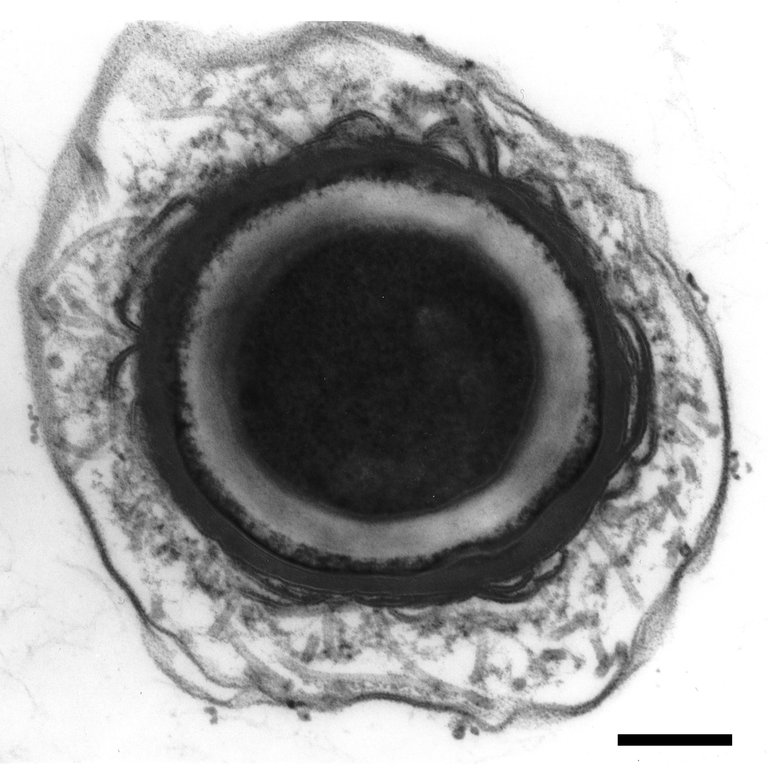

Lehenengo aurkikuntzetako bat izan zen neurotoxinaren informazioa duen genoma-zatia oso antzekoa dela bost anduietan. Horrek iradokitzen du bakterioak transferentzia bakarrean jaso zuela gene-multzo osoa. Izan ere, bakterioetan oso ohikoa da transferentzia horizontal deritzon prozesuaren bidez trukatzea geneak.

Toxina botulinikoaren informazio genetikoa duten eskualde berean, halaber, beste bi toxinaren informazio genetikoa aurkitu zuten ikertzaileek, baina dagoeneko funtzionalak ez direnak. Hori ikusita, ondorioztatu dute geneak trukatzeko “puntu bero” bat izan daitekeela genomaren eskualde hori.